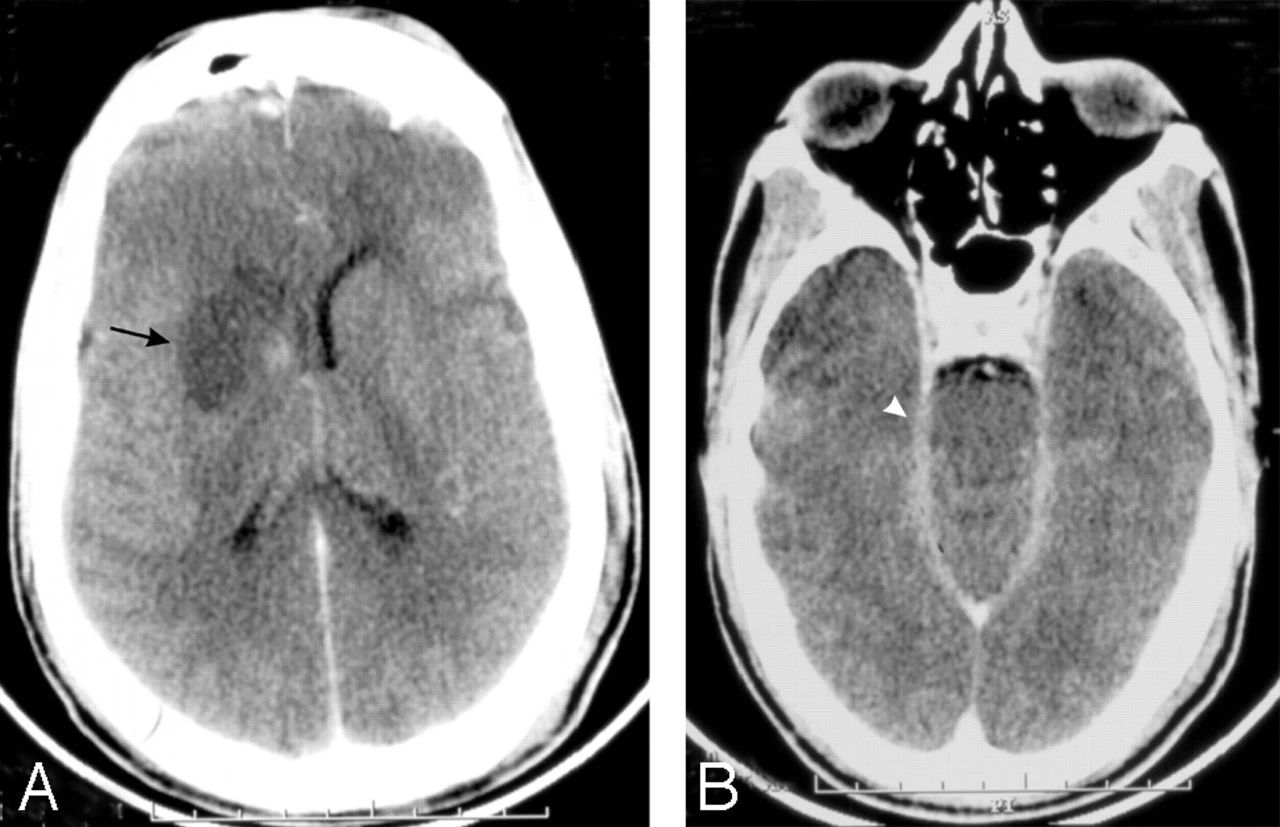

对比度增强的CT脑扫描显示右基底神经节梗塞(箭头,A)和增强的渗出物在脑内池(箭头,B)